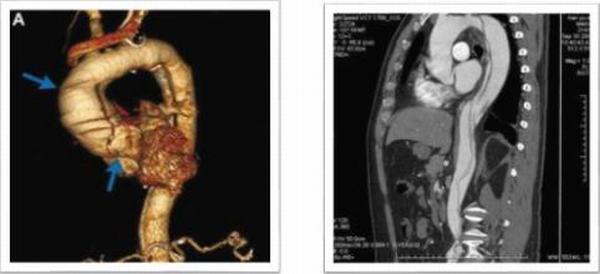

第一例患者31歲女性,運(yùn)動(dòng)員,有外傷史;主訴“反復(fù)胸痛2月,加重1小時(shí)”入院,入院后行主動(dòng)脈CTA提示:升主動(dòng)脈增寬,最寬處10.7cm,升主動(dòng)脈近主動(dòng)脈根部多發(fā)破口,最大破口直徑5.1cm,最小破口直徑0.64cm,主動(dòng)脈夾層動(dòng)脈瘤(A型)。心臟彩超:主動(dòng)脈夾層(A型)伴主動(dòng)脈瓣關(guān)閉不全,EF 50%,真腔內(nèi)血流進(jìn)入假腔,主動(dòng)脈瓣反流(大量)。心肌損傷標(biāo)志物正常,行術(shù)中探查破口累及主動(dòng)脈弓部及降部,手術(shù)方案:升主動(dòng)脈人工血管置換、主動(dòng)脈弓置換、降主動(dòng)脈支架植入、主動(dòng)脈瓣機(jī)械瓣膜置換手術(shù)順,利,術(shù)后第二天拔除氣管插管,第12天出院。

第二例患者36歲男性,職員,馬凡氏綜合癥;主訴“后背部疼痛3小時(shí)”入院,8年前因“馬凡氏綜合征、升主動(dòng)脈瘤并主動(dòng)脈伴關(guān)閉不全”在我科行Bentall手術(shù);入院后行主動(dòng)脈CTA提示:主動(dòng)脈夾層動(dòng)脈瘤(B型)合并主動(dòng)脈弓瘤樣擴(kuò)張,直徑7.0cm,主動(dòng)脈弓至左髂總動(dòng)脈雙腔影,內(nèi)膜片撕裂,并見多發(fā)破口,左側(cè)鎖骨下動(dòng)脈起始部受累,破口內(nèi)徑約0.83-1.28cm,腹腔干起自真假腔,腸系膜上動(dòng)脈假腔;左腎動(dòng)脈起自假腔,右腎動(dòng)脈起自真假腔;該病例為二次手術(shù)患者,且為夾層動(dòng)脈瘤伴弓部瘤樣擴(kuò)張。擬行全主動(dòng)脈弓置換、降主動(dòng)脈支架植入術(shù),手術(shù)順利,術(shù)后第二天拔除氣管插管,第14天出院,恢復(fù)良好。

第三例患者59歲男性,農(nóng)民,有“腹部疼痛7小時(shí),右下肢麻木5小時(shí)”入院,既往患有高血壓病10余年,腦出血病史8年;在當(dāng)?shù)乜h醫(yī)院行胸部增強(qiáng)CT提示:主動(dòng)脈夾層動(dòng)脈瘤(A型);救護(hù)車急診送來我院,急查主動(dòng)脈CTA:主動(dòng)脈夾層I型(主動(dòng)脈全程受累及)。心臟彩超:主動(dòng)脈夾層動(dòng)脈瘤(I型),主動(dòng)脈瓣關(guān)閉不全,心包積液(少量),血流往返于真腔與假腔之間,主動(dòng)脈瓣反流(大量)。該病例擬行Bentall、全主動(dòng)脈弓置換、降主動(dòng)脈支架植入術(shù),手術(shù)順利,術(shù)后第11天出院,恢復(fù)良好。